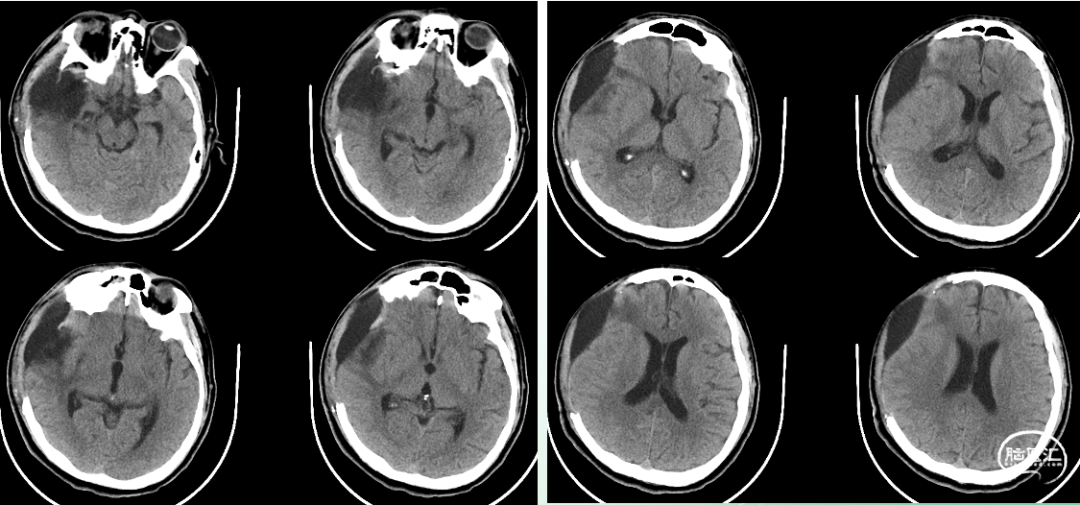

入院时影像

急诊颅脑CT+三维重建:

颅脑锐器损伤并异物存留,异物由右侧眼眶刺入颅内;右侧额颞叶挫裂伤并血肿形成;蛛网膜下腔出血;脑室系统较多积血;右侧额颞顶部少量硬膜下积血。